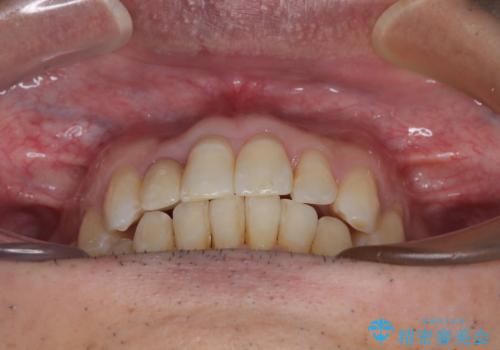

前歯のクラウンは変色が著しいため、矯正治療後にオールセラミッククラウンにて補綴治療を行うこととしました。

担当医としてはもう少し前歯のデコボコを改善したいところでしたが、患者様としては十分に満足いく歯列であり、マウスピース矯正に飽きてしまったとのことで、治療終了となりました。